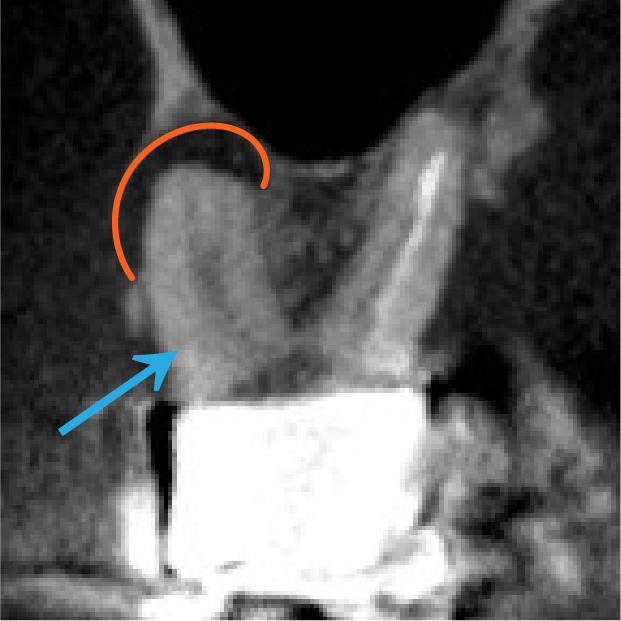

CTで詳しく調べることで、歯の中にいくつかある根の管(根管)のうち、どこに細菌が入り込んで炎症を起こしているのか(赤い部分)を確認できます。

また、根の管がどの方向に曲がっているのか、どのような形をしているのか(青い矢印部分)を立体的に見ることができるため、より確実で安全な治療につながります。

治療後は、青い矢印で示した根管がしっかり治療され、赤い部分に見られた黒い影(炎症)が小さくなっており、改善してきていることが確認できます。